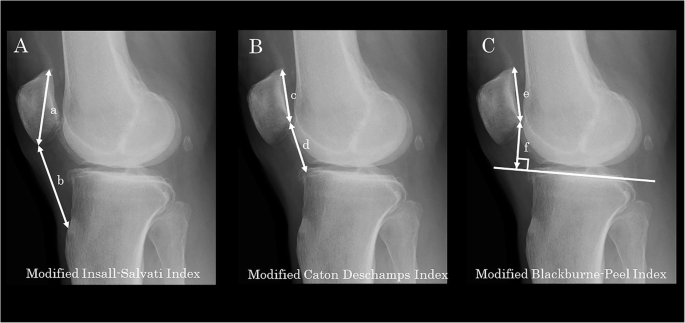

The patellar height on the sagittal plane was assessed on the weight-bearing lateral radiograph in an extended position. The patellar height was measured on the standing lateral radiograph in an extended position. In their original descriptions, the Insall–Salvati [14], Caton–Deschamps [15], and Blackburne–Peel [16] indices were based on the measurement of the nonweight-bearing lateral radiograph in mild degrees of flexion (30°). The assessment in an extended position in this study may have been associated with reduced tension in the extensor mechanism and slackness of the patellar tendon leading to potential inaccuracy in assessment of the patellar height. As for the analytical parameters, the modified Insall–Salvati Index (mISI), modified Caton–Deschamps Index (mCDI), and modified Blackburne–Peel Index (mBPI) [6] were measured (Fig. 2).

Measurements of patellar height on a standing lateral radiograph. A Modified Insall–Salvati index (b/a), defined as the value obtained by dividing the patellar tendon length (b, from inferior pole of the patella to the distal insertion of the patellar tendon at the tibial tubercle) by the maximum length of the diagonal length of the patella (a). B Modified Caton–Deschamps index (d/c), defined as the value obtained by dividing the distance from the distal end of the articular surface of the patella to the angular protrusion of the tibial plateau (d) by the length of the patellar articular surface (c). C Modified Blackburne–Peel index (f/e), defined as the value obtained by dividing the length of the perpendicular line from the lowest pole of the patellar articular surface to the surface of the tibial plateau (f) by the length of the patellar articular surface (e)